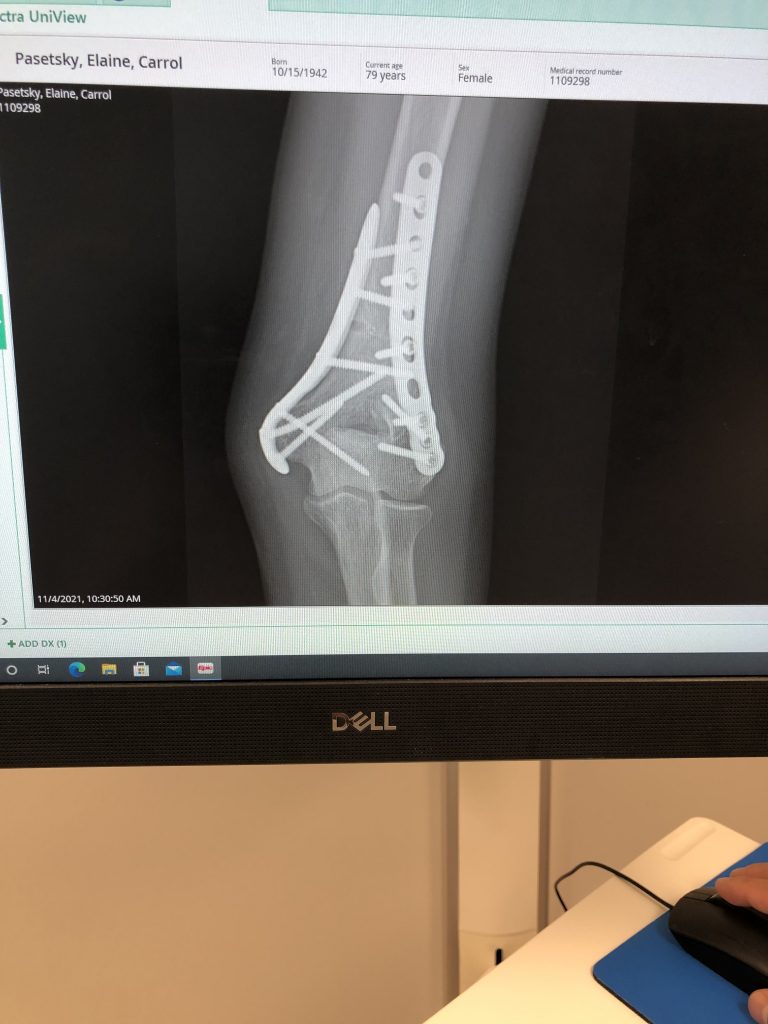

Dr. Sama is a skilled surgeon that is a master in repair. He used plastic surgery stitches upon closing the wound. This picture is 11 weeks into healing and you can barely notice. I have returned to 100% functioning to the surprise of PT and myself. I am so grateful to this wonderful surgeon who is also compassionate and generally a really nice guy. Thank you.